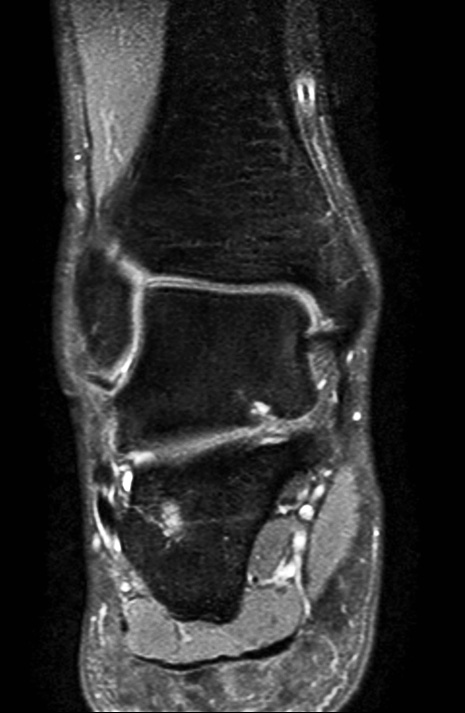

Coronal PDw mDIXON TSE (In Phase)